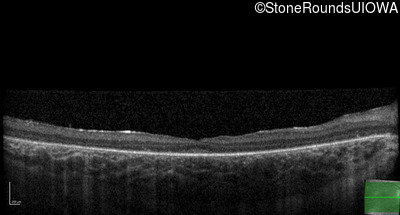

Age at visit: 10 years

OD OS